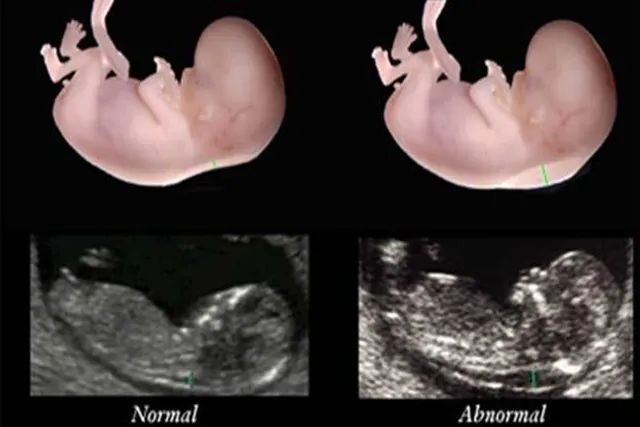

03那么怀孕三个半月的胎儿,发育成什么样了呢?

每个精子想要与卵子“相遇”,都要经历比九九八十一难还艰苦的过程。那么多的精子,不仅要保持活力,还要维持高质量并且走对输卵管,才能与卵子顺利结合为受精卵。在成为受精卵以后,它们才开始慢慢在女性子宫内找到温暖适宜发育的地方进行着床。

但这时,还只能称之为胚胎,胚胎发育所需的营养需要从母体获得。在孕三个月的时候,胚胎才成长为胎儿。

这时胎儿已经开始出现眼睛、鼻子等器官了,而且就连手指、脚等部位也能清晰的分辨出来。看起来就是一个正常的宝宝,非常可爱。